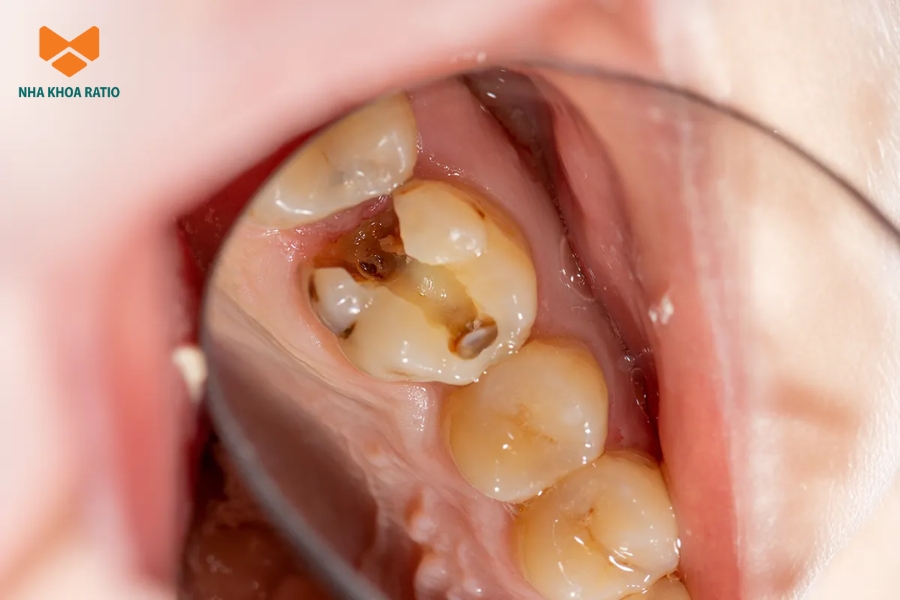

Bệnh nhân sẽ được bác sĩ chỉ định điều trị tủy khi vi khuẩn đã xâm nhập vào mô tủy và gây ra tình trạng viêm hoặc nhiễm trùng.

- Sâu răng lan rộng, kèm theo vùng nướu đổi màu.

Bên trong mỗi chiếc răng có một khoang nhỏ chứa mô tủy. Mô này kéo dài từ thân răng xuống đến vùng chóp và bao gồm dây thần kinh, mạch máu cùng các tế bào liên kết giúp duy trì sức sống của răng. Khi răng bị sâu, nứt hoặc sứt, vi khuẩn có thể đi vào khoang tủy và gây viêm.

Khi tủy răng đã bị tổn thương, nó không thể tự hồi phục. Vi khuẩn tiếp tục phát triển bên trong tủy khiến mô bên trong sẽ phân hủy dần, tạo điều kiện cho ổ mủ hình thành quanh chóp và khiến xương hàm bị tiêu. Nếu không được điều trị kịp thời, giai đoạn muộn có thể dẫn đến chết tủy và mất răng.